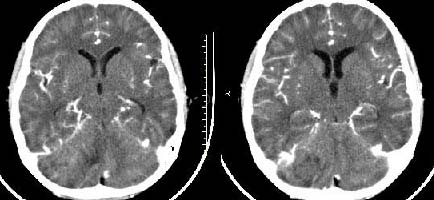

以下是引用子期在2009-6-10 21:34:00的发言:[br]髓母细胞瘤一般位于中线附近和小脑蚓部,该病灶位于右侧小脑半球,倾向于毛细胞型星形细胞瘤,当然也不能完全排除髓母细胞瘤。

以下是引用随光逐影在2009-6-10 22:26:00的发言:[br]考虑右侧小脑胶质瘤,髓母细胞瘤待排。

以下是引用影象小泰斗在2009-6-10 22:14:00的发言:[br]年龄及影像表现军符合小脑星形细胞瘤表现![br]期待病理结果!